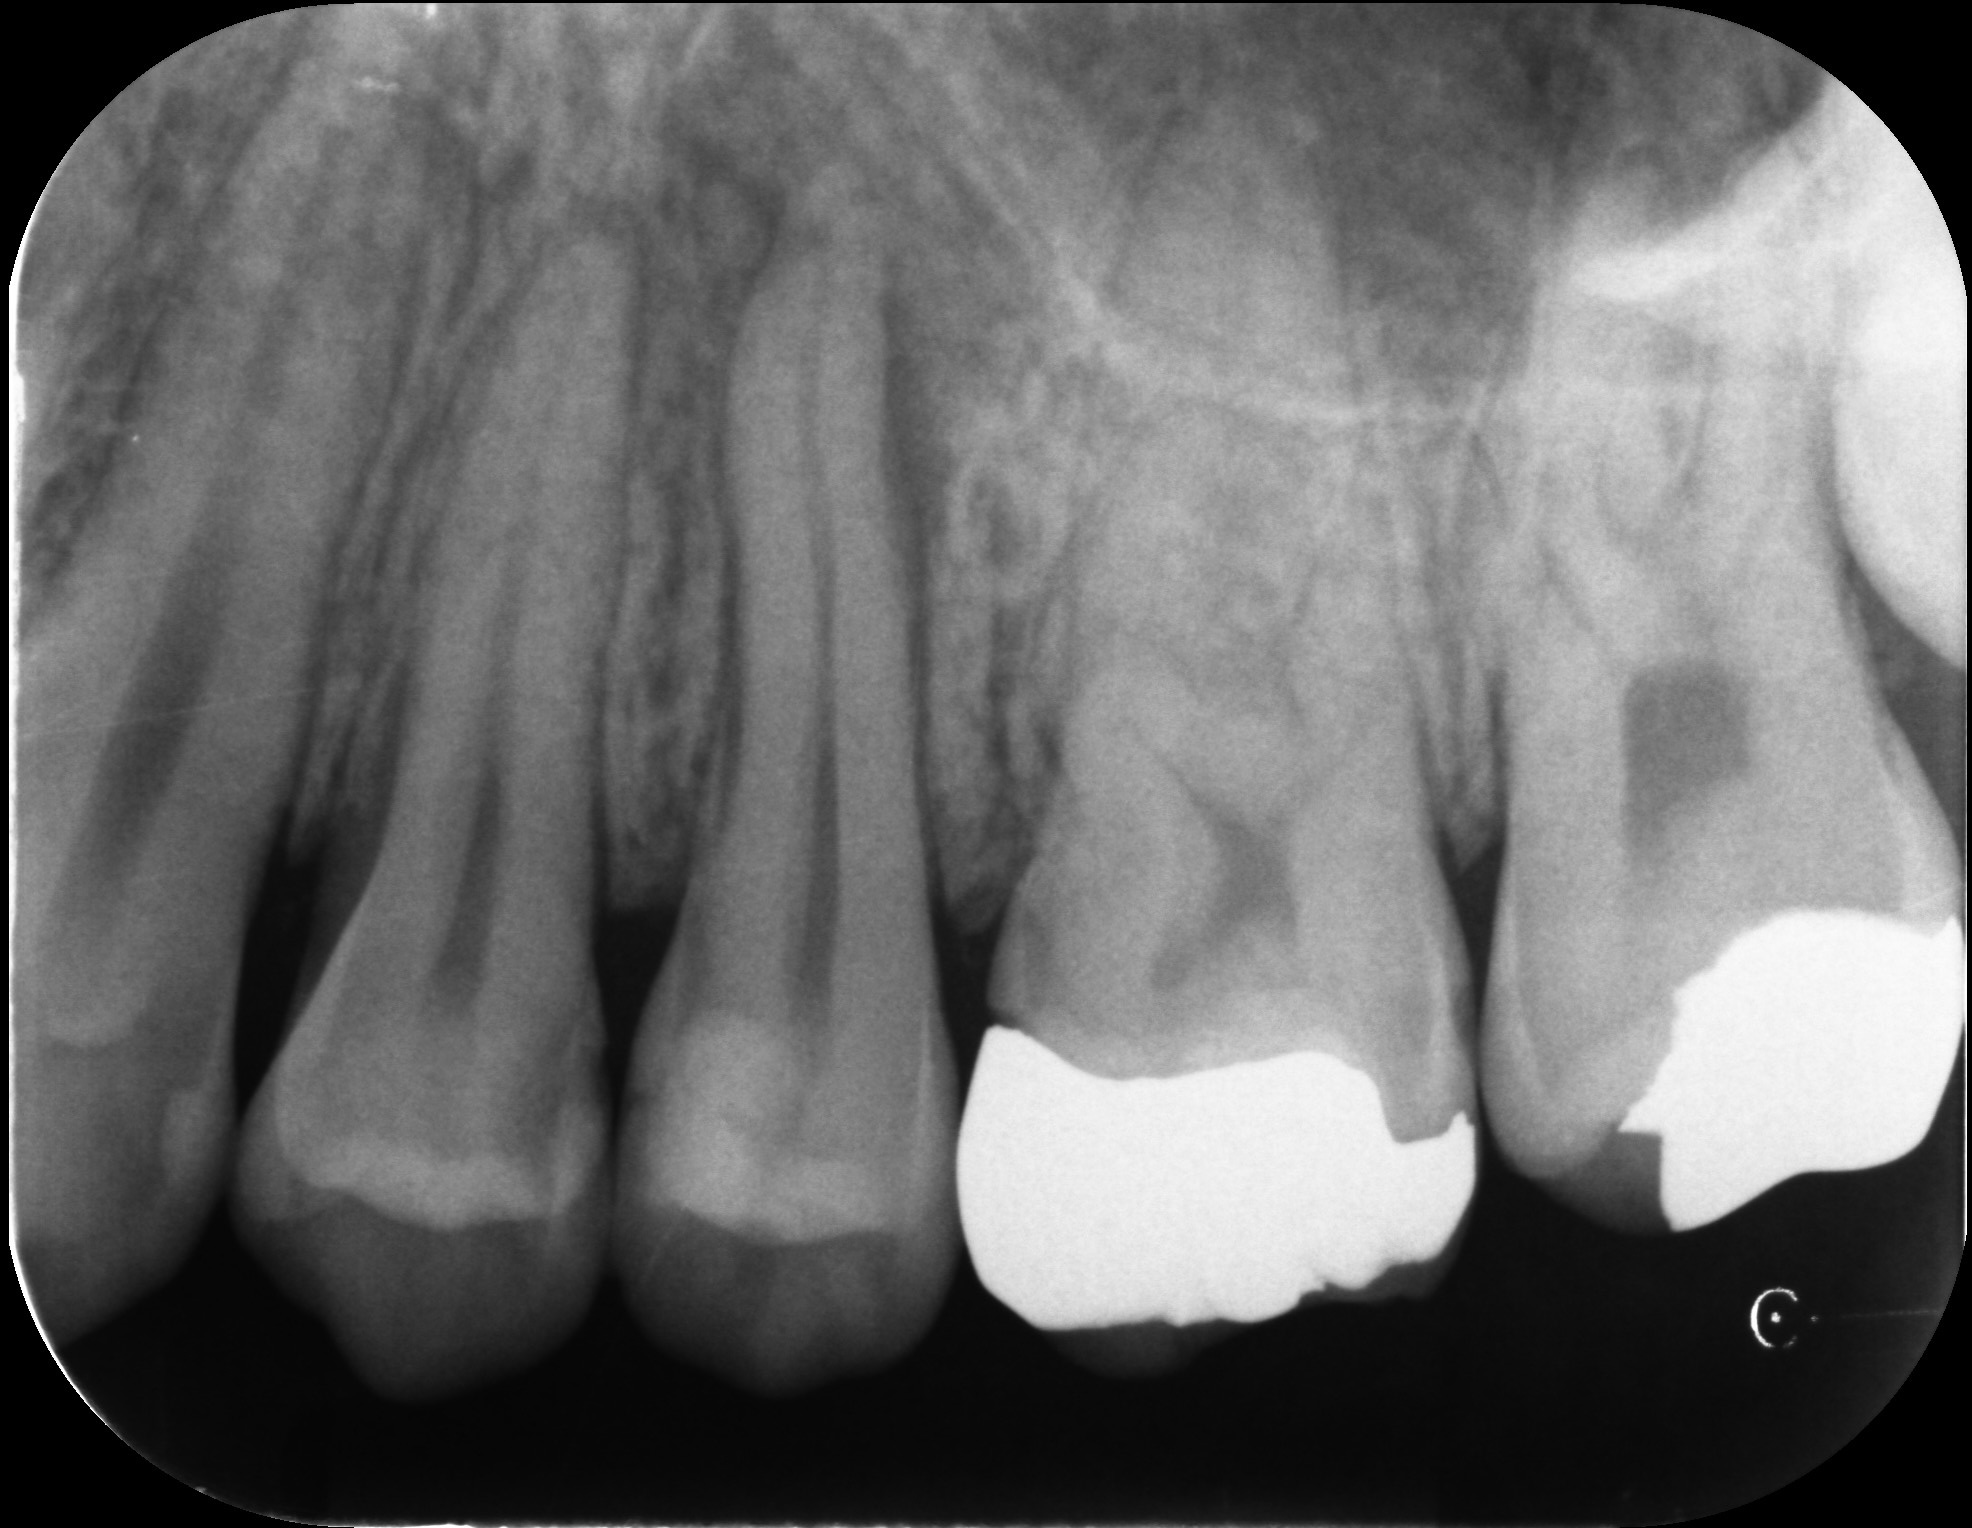

再根管治療で奥歯を残した症例

タップで写真の拡大ができます。

Before

After

主訴

噛むと違和感がある。

治療内容

リトリートメント(再根管治療・大臼歯)

ファイバーポストコア

治療期間

1ヶ月

治療費用

198,000

治療の

リスク

根尖部透過像が完全に消失しない可能性があります。